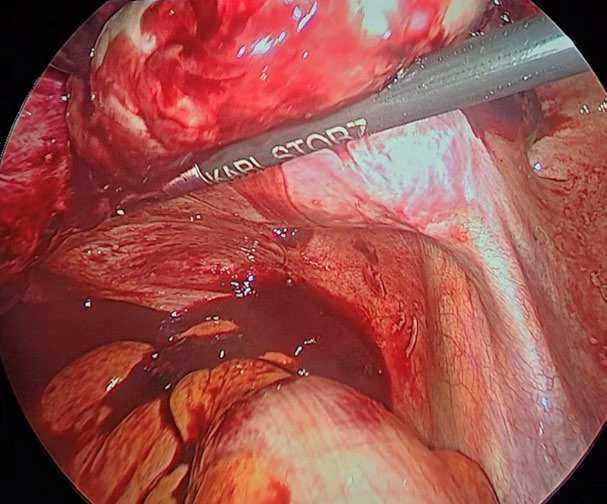

The Gynecological Endoscopy service evaluated the patient and recommended a laparoscopy with salpingostomy to preserve fertility and tubal patency. During surgery, an enlarged uterus was found, with ectopic pregnancy located in the right tube, in the ampullary region, there was a ruptured ectopic pregnancy, measuring 2 x 2 centimeters and associated with a hemoperitoneum of approximately 100 milliliters. A salpingostomy was performed with removal of the embryonic tissue located at the anterior edge of the fallopian tube, using Grasper forceps and a suction and irrigation device. Vasopressin was infiltrated, diluting 20 international units in 100 milliliters of physiological solution, to minimize bleeding. The fallopian tube was then transected to extract the pregnancy using a 5-millimeter trocar, again using the Grasper forceps. In addition, multiple adhesions were identified and released. No intraoperative incidents were reported, as the procedure was performed by a surgeon experienced in minimally invasive surgery. Estimated bleeding during the procedure was 50 milliliters, and the approximate duration of the intervention was 60 minutes. (Figure 1-5).

Figure 2: salpingostomy was performed with removal of the embryonic tissue located at the anterior edge of the fallopian tube, using a grasper forceps, a suction and an irrigation device